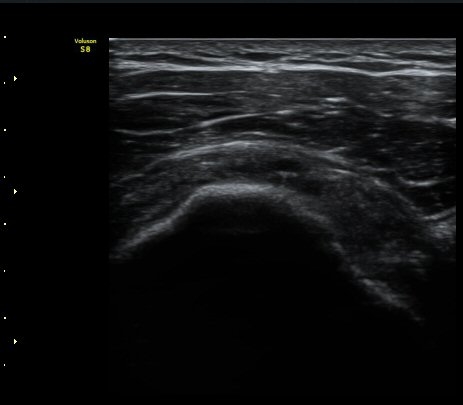

ÀÌµÎ¹Ú±Ù°Ç È¾´Ü¸é°Ë»ç¿¡¼­ ƯÀÌ ¼Ò°ß ¾øÀ½

(no specific abnormal findngs with transverse scan of biceps tendon) »çÁø 1, 2